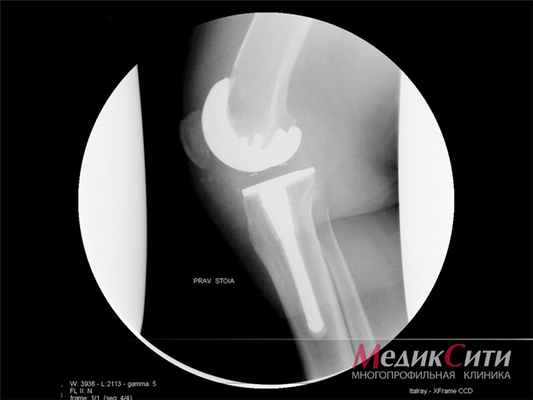

На поздних стадиях заболевания при неадекватной либо поздней терапии, при агрессивном течении болезни иногда необходимы хирургические методы лечения, восстанавливающие функцию конечностей. Видами хирургической коррекции при РА являются - синовэктомия (удаление синовиальной оболочки пораженного сустава), реконструктивные операции на костях, связках, сухожилиях крупных и мелких суставов (пластика), а также эндопротезирование.

В Клинике высоких медицинских технологий им. Н. И. Пирогова при подозрении на РА пациенты после осмотра врача-ревматолога могут пройти полное обследование , включая все лабораторные тесты, Rg суставов, при необходимости МРТ суставов и другие методы исследования внутренних органов при наличии показаний. Ревматолог назначит адекватную терапию и в последующем будет осуществляться оценка эффективности и переносимости лечения, динамическое наблюдение за пациентом. Также в нашем учреждении пациенты могут получить консультацию физиотерапевта и врача ЛФК, и пройти при наличии показаний и отсутствии противопоказаний различные виды физиолечения, массажа и т. д. После квалифицированной консультации ортопеда-травматолога совместно с ревматологом и врачами других специальностей пациентам, с учетом показаний к оперативному лечению суставов, выполняются различные виды оперативных вмешательств.